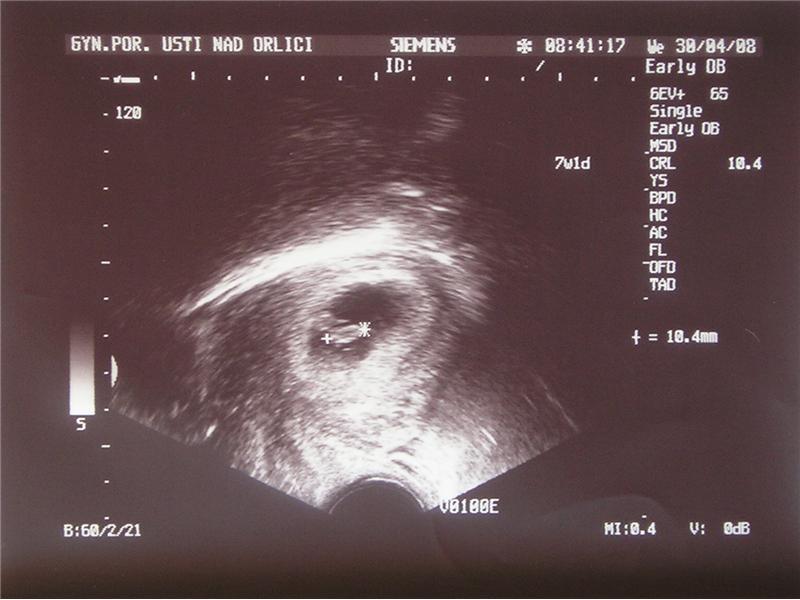

Ultrazvuk